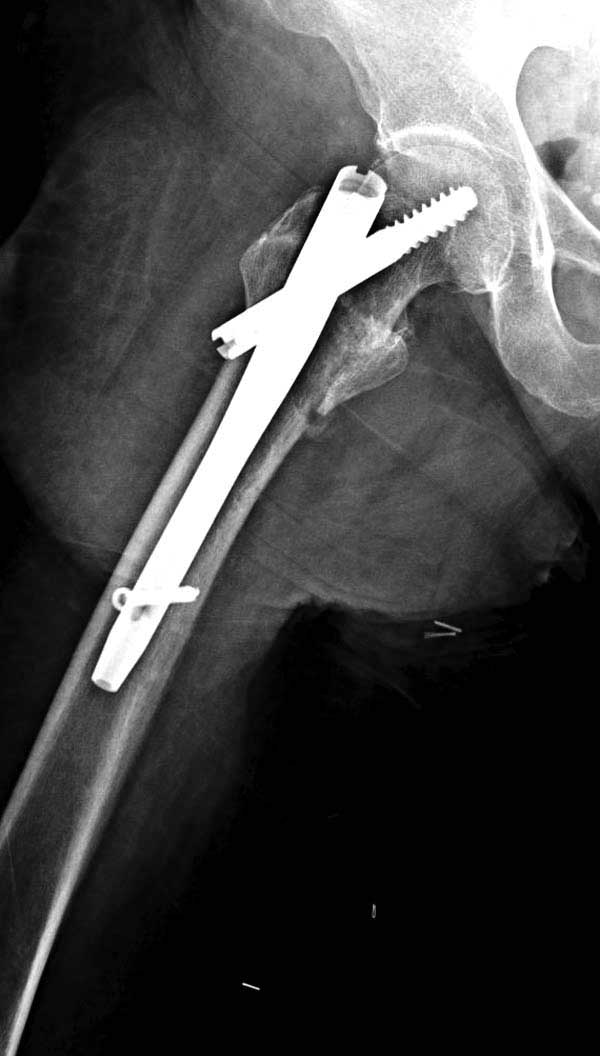

Повторно поступает после двух с половиной лет, где обнаруживается перелом на второй стороне. Немного сложно, но для фиксации выбрали Antegrade InterTan Smith Nephew Nail и с момента фиксации более 3х мес.

Имя     : 32 IT fx LT injury CRM1.JPG

Тип     : image/jpg

Размер  : 26962 байтов

Описание: отсутствует

Url     : http://weborto.net:8080/pipermail/ortho/attachments/20120510/52aada75/attachment-0052.jpg